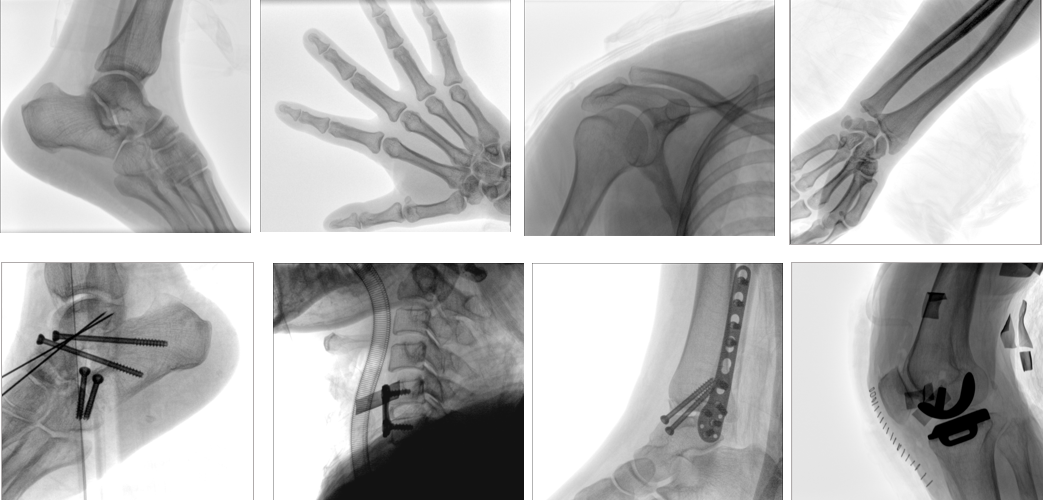

【產(chǎn)品臨床圖片】

PLX118F移動式平板C形臂X射線機臨床應用范圍:骨科、普通外科、矯形外科、創(chuàng)傷外科、泌尿外科、脊柱外科、疼痛外科、消化科、腫瘤科、婦產(chǎn)科等科室。